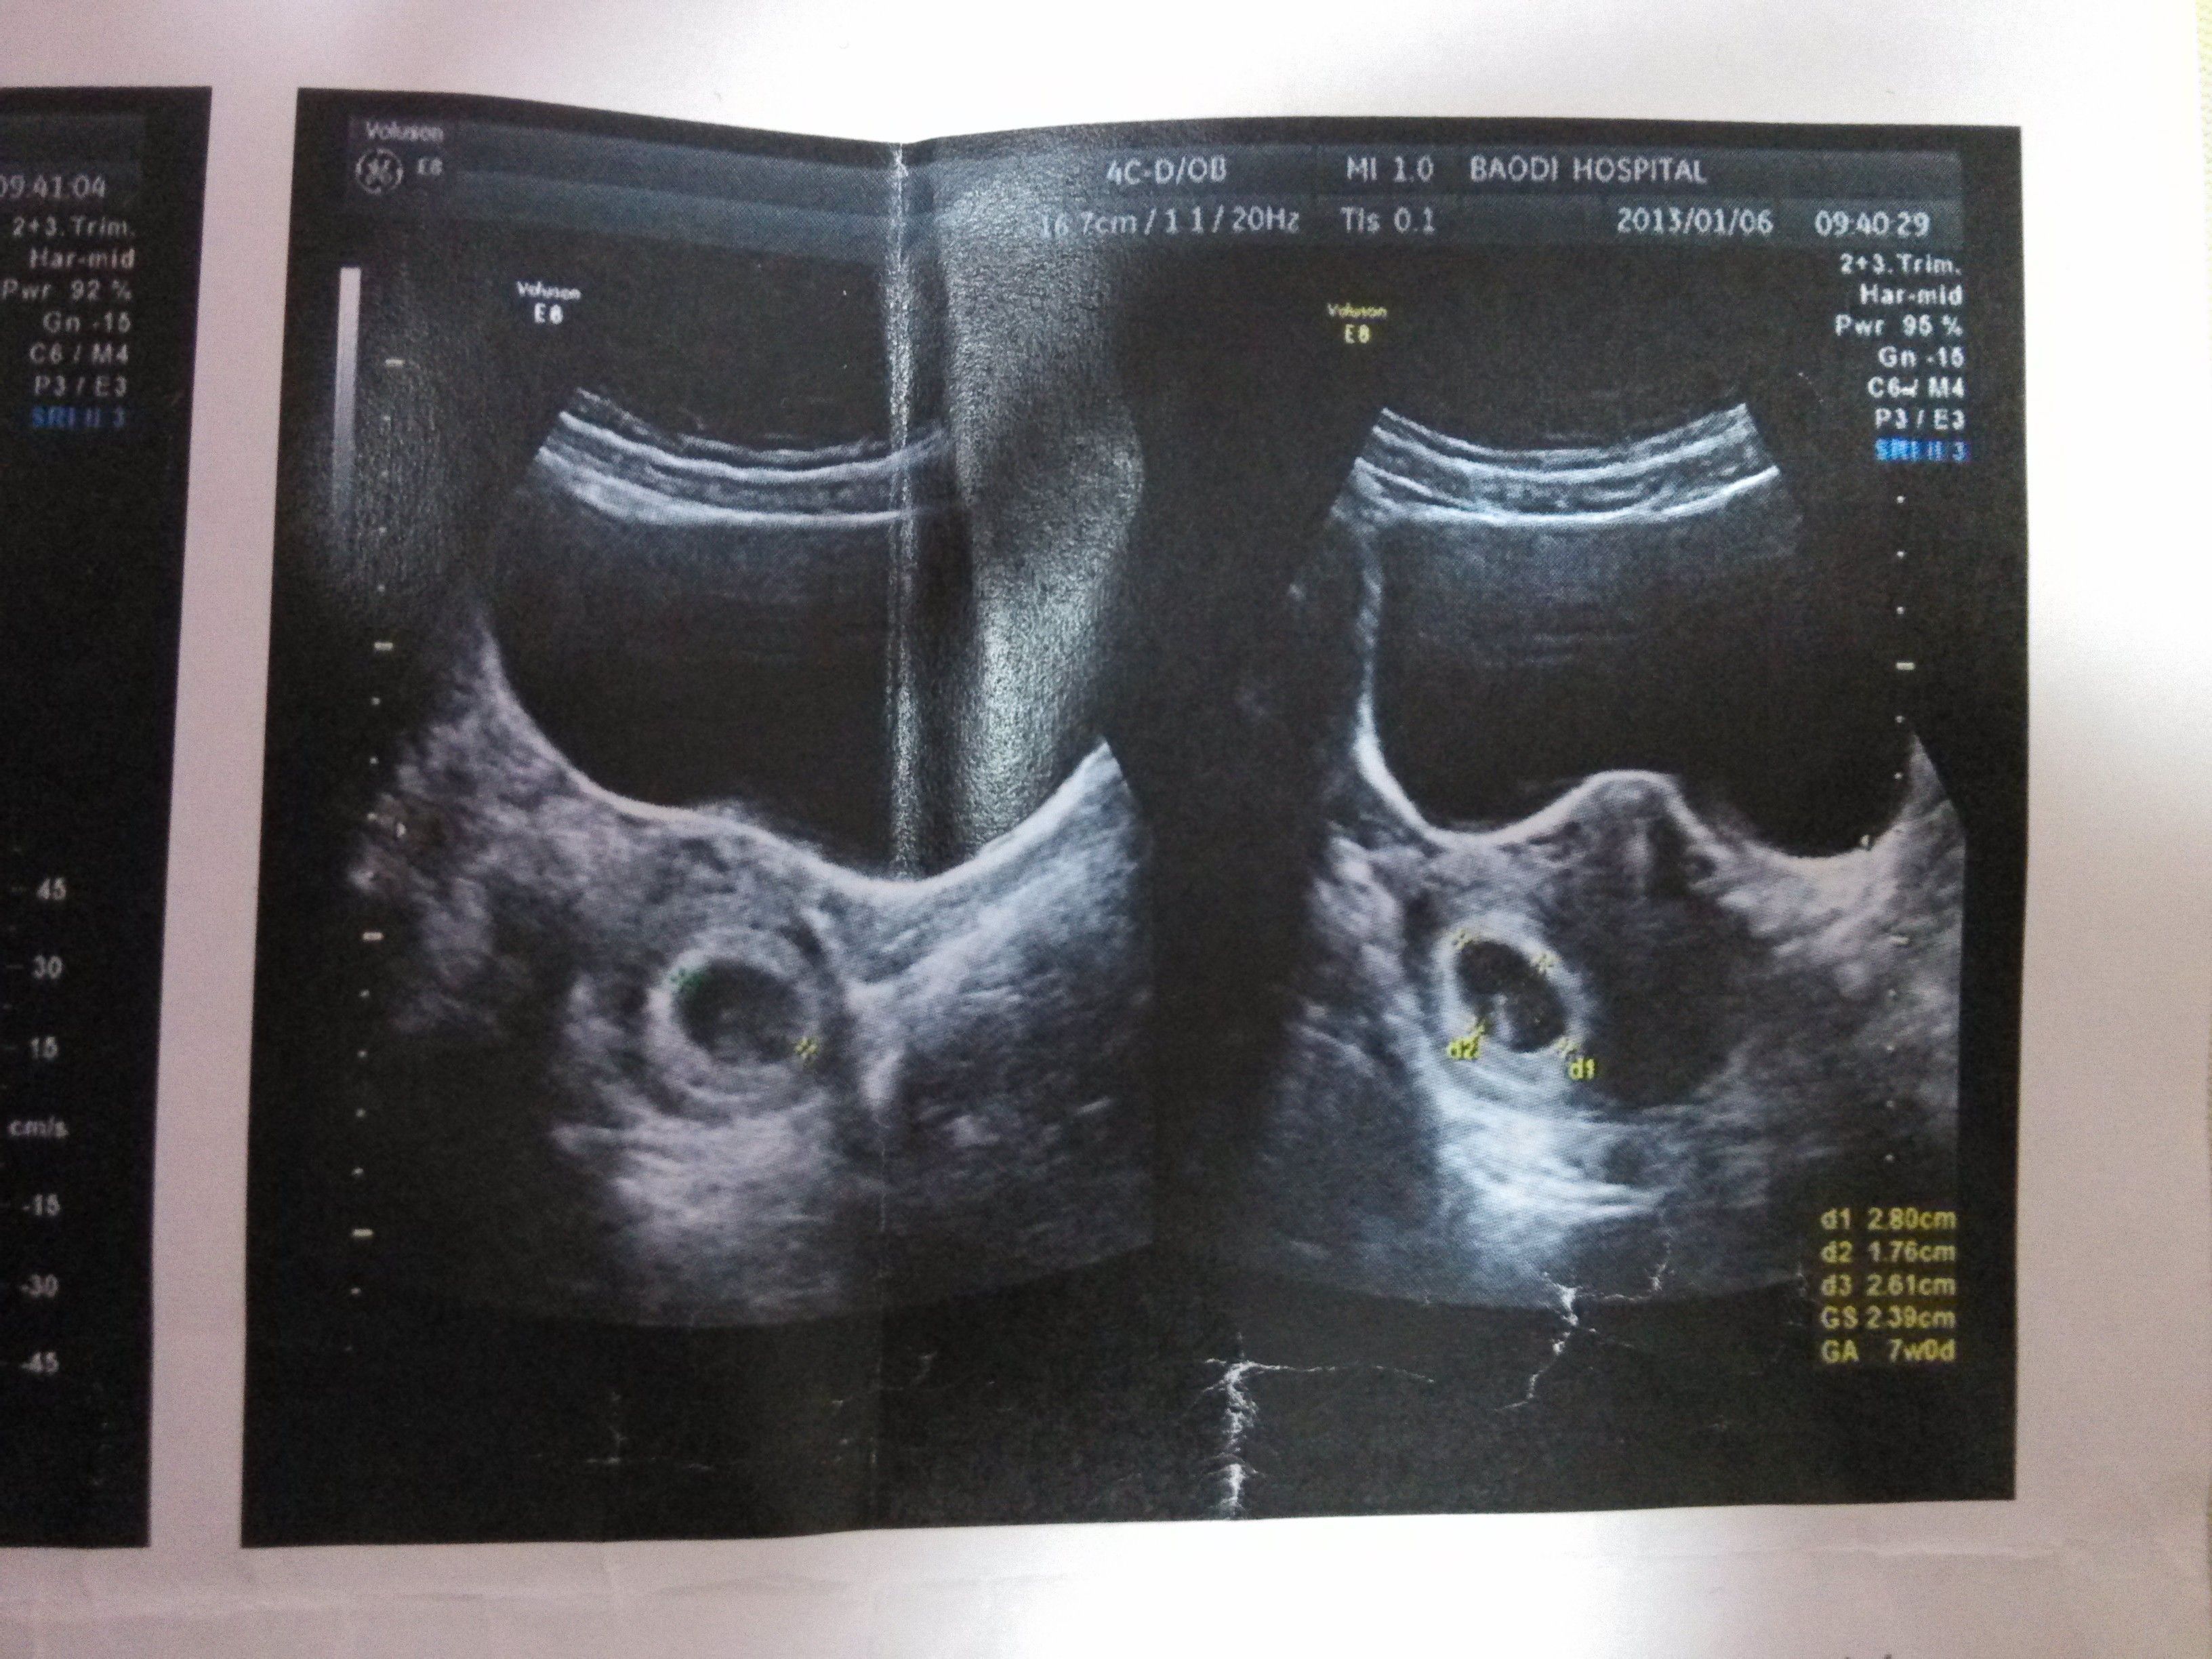

怀孕49天B超数据 d1:2.80cm d2:1.76cm d3:2.61cm GS:2.39cm GA: 7WOD 求高人看看男女